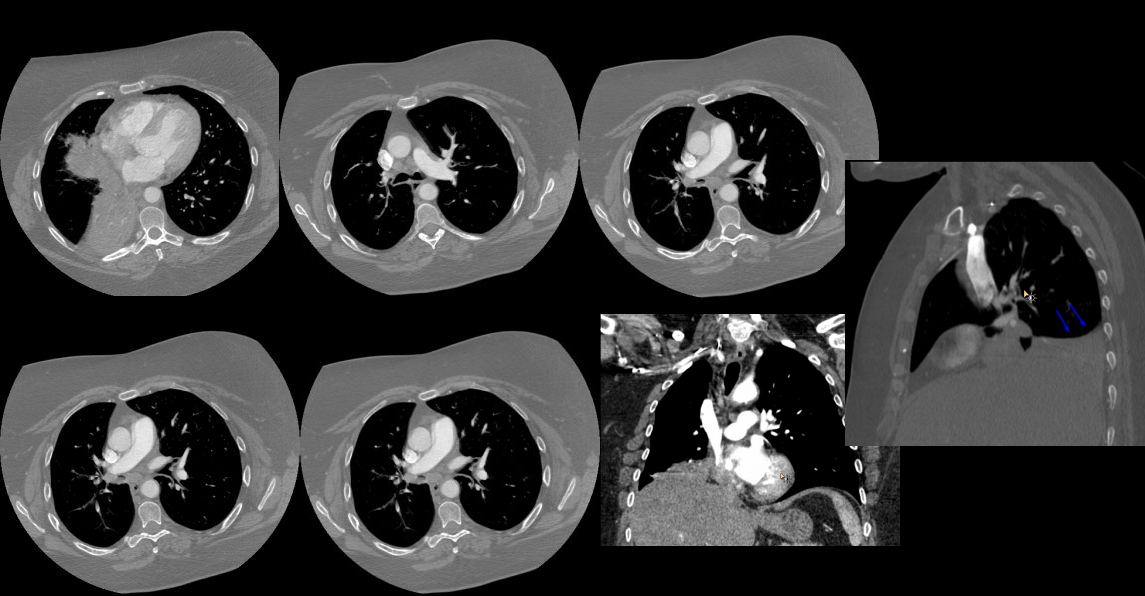

Age: 55

Sex: Female

Indication: Hemoptysis

Sample ReportRight middle and lower lobe collapse. Recommend chest CT to assess for a central obstructing mass.

No pleural effusion.